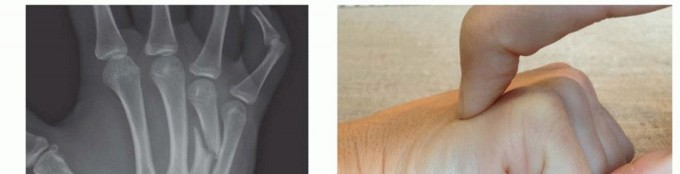

TECH FIG 4 • A-C. Patient with torsional injury to long and ring fingers leading to spiral fractures of the third and fourth metacarpals. The combined injury made it possible for malrotation to develop. D.

TECH FIG 4 • (continued) G,H. Motion at 6 weeks after surgery. The periosteum is elevated at the fracture site to assist with assessment of fracture reduction. As much of the interosseous muscle is left attached to the metacarpal as feasible to preserve blood supply to the bone.The fracture is reduced and provisionally stabilized with reduction clamps (TECH FIG 4D).

LAG SCREW FIXATION

Long oblique and spiral fractures whose lengths are at least twice the diameter of the bone at the level of the fracture are amenable to limited fixation with screws only (see TECH FIG 4A-C).Appropriately sized lag screws (1.4 to 2.7 mm) are placed. Typically, two or three screws are used (TECH FIG 4E,F).The first screw is placed perpendicular to the fracture in order to compress it and the second screw is placed perpendicular to the bone to resist longitudinal forces.In order to get proper compression with a lag screw construct, it is important to overdrill the near cortex.When using a 2.0-mm screw system, a 1.5-mm drill bit is used to drill both cortices. The near cortex is then overdrilled with a 2-mm drill bit.A countersink is used to maximize contact between the head of the screw and the bone. The size of the screw is measured and an appropriately sized screw is placed.The periosteum and interosseous muscle fascia are reapproximated to cover the screws. The juncturae tendinum are repaired and the skin is closed in standard fashion.The hand is then immobilized with the MP joints flexed 70 to 90 degrees with a forearm-based splint. Early motion can be started as early as 4 to 7 days, depending on fracture stability (TECH FIG 4G,H).